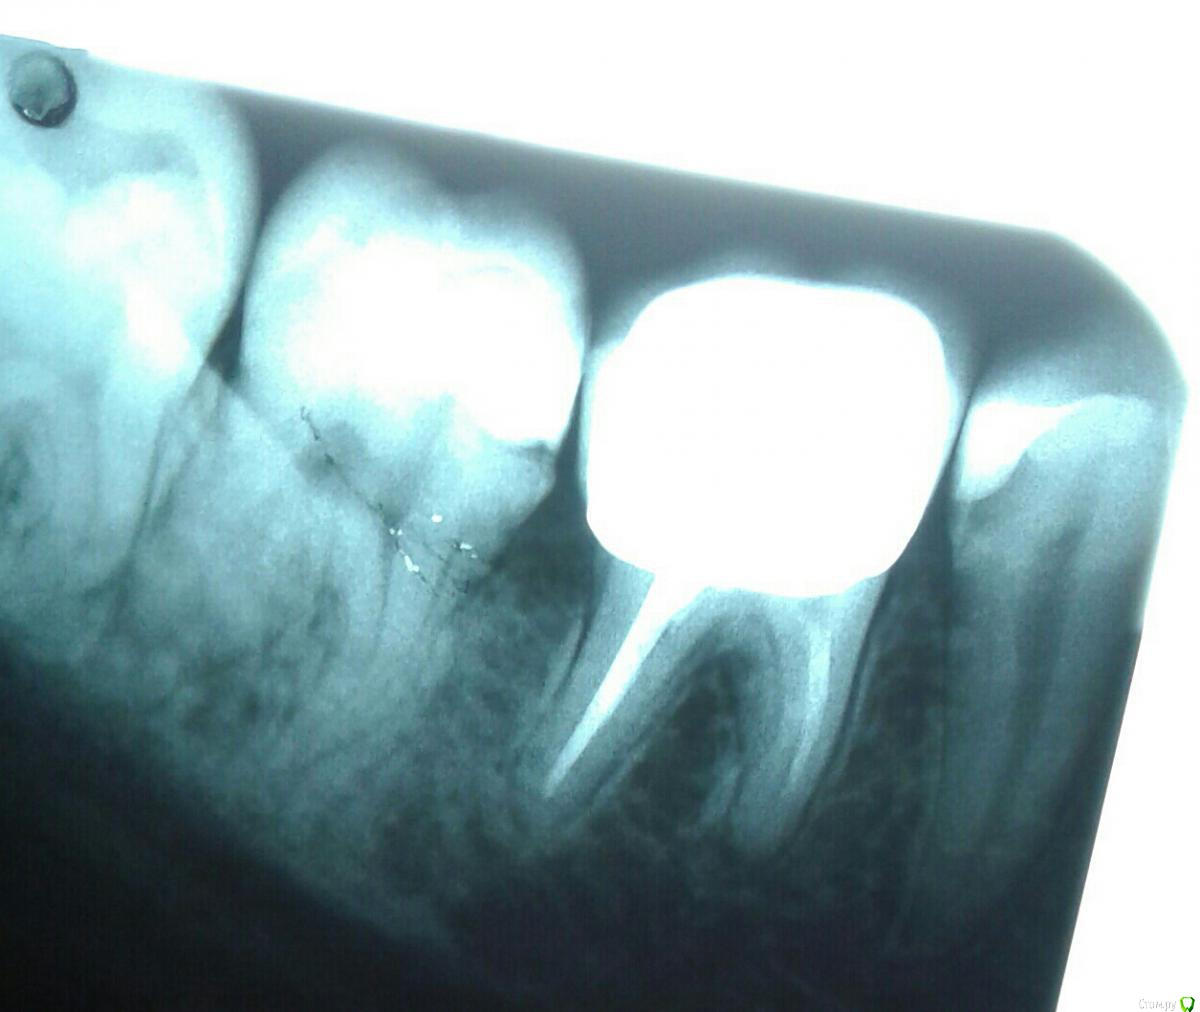

Инна2106 Опубликовано 27 июля, 2018 Поделиться Опубликовано 27 июля, 2018 (изменено) Добрый день.Прошу помочь определить в чем может быть причина ситуации с зубом которая длиться уже две недели.Началось все в ночь 13 августа проснулась от боли в одном участке нижней челюсти, именно не зубе, а челюсти, боль не острая, а тупая ноющая. Встала, походила все прошло. Весь день ничего не болело. В ночь все повторилось уже дважды просыпалась от боли, не определенного зуба, а низа левой челюсти. Для снятия боли достаточно было просто походить в течении 5 минут, все успокаивалось.На следующий день пошла к врачу, сделал снимок, осмотрел, сказал, что есть небольшая гранулема под шестым зубом под коронкой из-за не до конца запломбированного канала, но это как оказалось старая проблема, определялась еще на ортопанораме зимой. Но по его словам она не может давать такого рода болей. Ночью не спала вообще, четыре раза вставала от болей, причем стоило только принять горизонтальное положение и начиналась ноющая боль в нижней челюсти слева, и потом верхней челюсти слева. Суть в том что боли появлялись именно когда ложилась, не важно днем или ночью, пока ходишь, сидишь ничего не беспокоило. Снова поехала на прием к врачу, сделал много проб, и воздухом и нитью, подозревал трещину по снимку рядом в зубе под пломбой, но сказал нить не цепляется и не рвется значит ее нет, но вскрывать этот зуб не смысла так как на простукивание все было спокойно и сверху и снизу. Десна все розовые, кровоточивости нет. Через три дня поехала к другому врачу сделал свой снимок, предположил как вариант что восьмерка может двигать зубной ряд оттуда и боль, но сама восьмерка абсолютно спокойна, не болит, нет отечности десны. Его заключение, что причина в троичном нерве, а не в зубах. До этого по рекомендации первого врача принимала Азитромицин 3 дня и Нимесил не помогло. Начала пить Нейродикловит (диклофенак с витаминами группы В) и наконец-то начала ночью спать, но с понедельника 23 июля начал болеть зуб при накусывании рядом с коронкой (семерка), я на эту сторону и так не ем уже две недели, почувствовала боль при пережевывании пищи. когда верхних зуб попадал на нижний, попробовала постучать ложкой и ощутила боль в семерке снизу. В среду поехала к третьему врачу, он сделал пришлифовку семерки нижней с верхней так как нагрузка на зуб неправильно распределялась на одно сторону, порекомендовал попить Нимесил и наблюдать.Суть в том, что на данный момент исчезли боли в горизонтальном положении, но не могу жевать и есть нормально, сам зуб не болит, но если попробовать накусить слегка зубочистку на семерку появляется боль, отпускаешь проходит.Очень прошу помогите разобраться что это и как себе помочь, скоро нужно уезжать и не знаю стоит ли сейчас снимать коронку или все же причина не в этом зубе. Стоит ли делать КТ, новую ортопанораму, если по снимкам ничего не видят. Внизу прикрепила фрагмент ортопанорамы делала в феврале этого года, и нашла снимок этого сделанный в конце апреля прошлого года для сравнения.Заранее большое спасибо. Изменено 27 июля, 2018 пользователем Инна2106 Ссылка на комментарий

Инна2106 Опубликовано 27 июля, 2018 Автор Поделиться Опубликовано 27 июля, 2018 Еще снимок Ссылка на комментарий

kramer Опубликовано 27 июля, 2018 Поделиться Опубликовано 27 июля, 2018 (изменено) Да банально пульпит нижней семерки. Там кариес под пломбой, видно же. Изменено 27 июля, 2018 пользователем kramer 1 Ссылка на комментарий

red_butler Опубликовано 27 июля, 2018 Поделиться Опубликовано 27 июля, 2018 Да банально пульпит нижней семерки. Там кариес под пломбой, видно же. тут кандидатов на пульпит прорва 2 Ссылка на комментарий

kramer Опубликовано 27 июля, 2018 Поделиться Опубликовано 27 июля, 2018 Про пульпит я у всех трех врачей с самого начала спрашивала, все его отрицают, так как нет реакции на холодное, горячее, воздух, зуб не болит все это время, появилась только реакция по накусывание и простукивание. По Вашему мнению нужно удалить нерв в семерке и боль пройдет? Как и сказано было выше, я насчитал с этой стороны 5 зубов, которые могут давать такую симптоматику, но из них 7ка наиболее вероятно. Ссылка на комментарий

kramer Опубликовано 27 июля, 2018 Поделиться Опубликовано 27 июля, 2018 (изменено) когда смотришь на снимок зубов два корня и два канала, на 6 и 8-м зубах это четко видно в 7-м один видно второй не ясно где, визуально. Эта трещина на снимке под пломбой и есть кариес? Я не знаю, куда вы смотрите, но мне видно все Трещина на снимке не может быть определена. А вот кариес видно. Он прям под пломбой. Изменено 27 июля, 2018 пользователем kramer Ссылка на комментарий